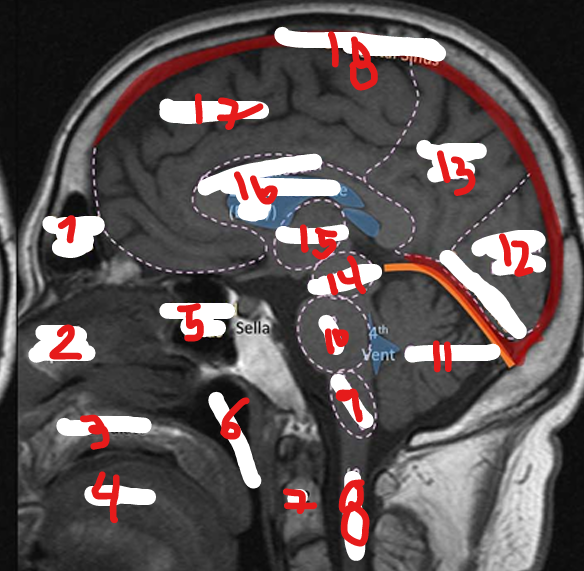

FRONTAL LOBE

1

New cards

PARIETAL LOBE

<p>2</p>

TEMPORAL LOBE

9

4

<p>5</p>

CEREBRUM

12

7

17

MEDULLA

PONS

10

CEREBELLUM

11

OCCIPITAL LOBE

13

MIDBRAIN

14

THALAMUS

15

CORPUS CALLOSUM

16

SUPERIOR SAGITAL SINUS

18